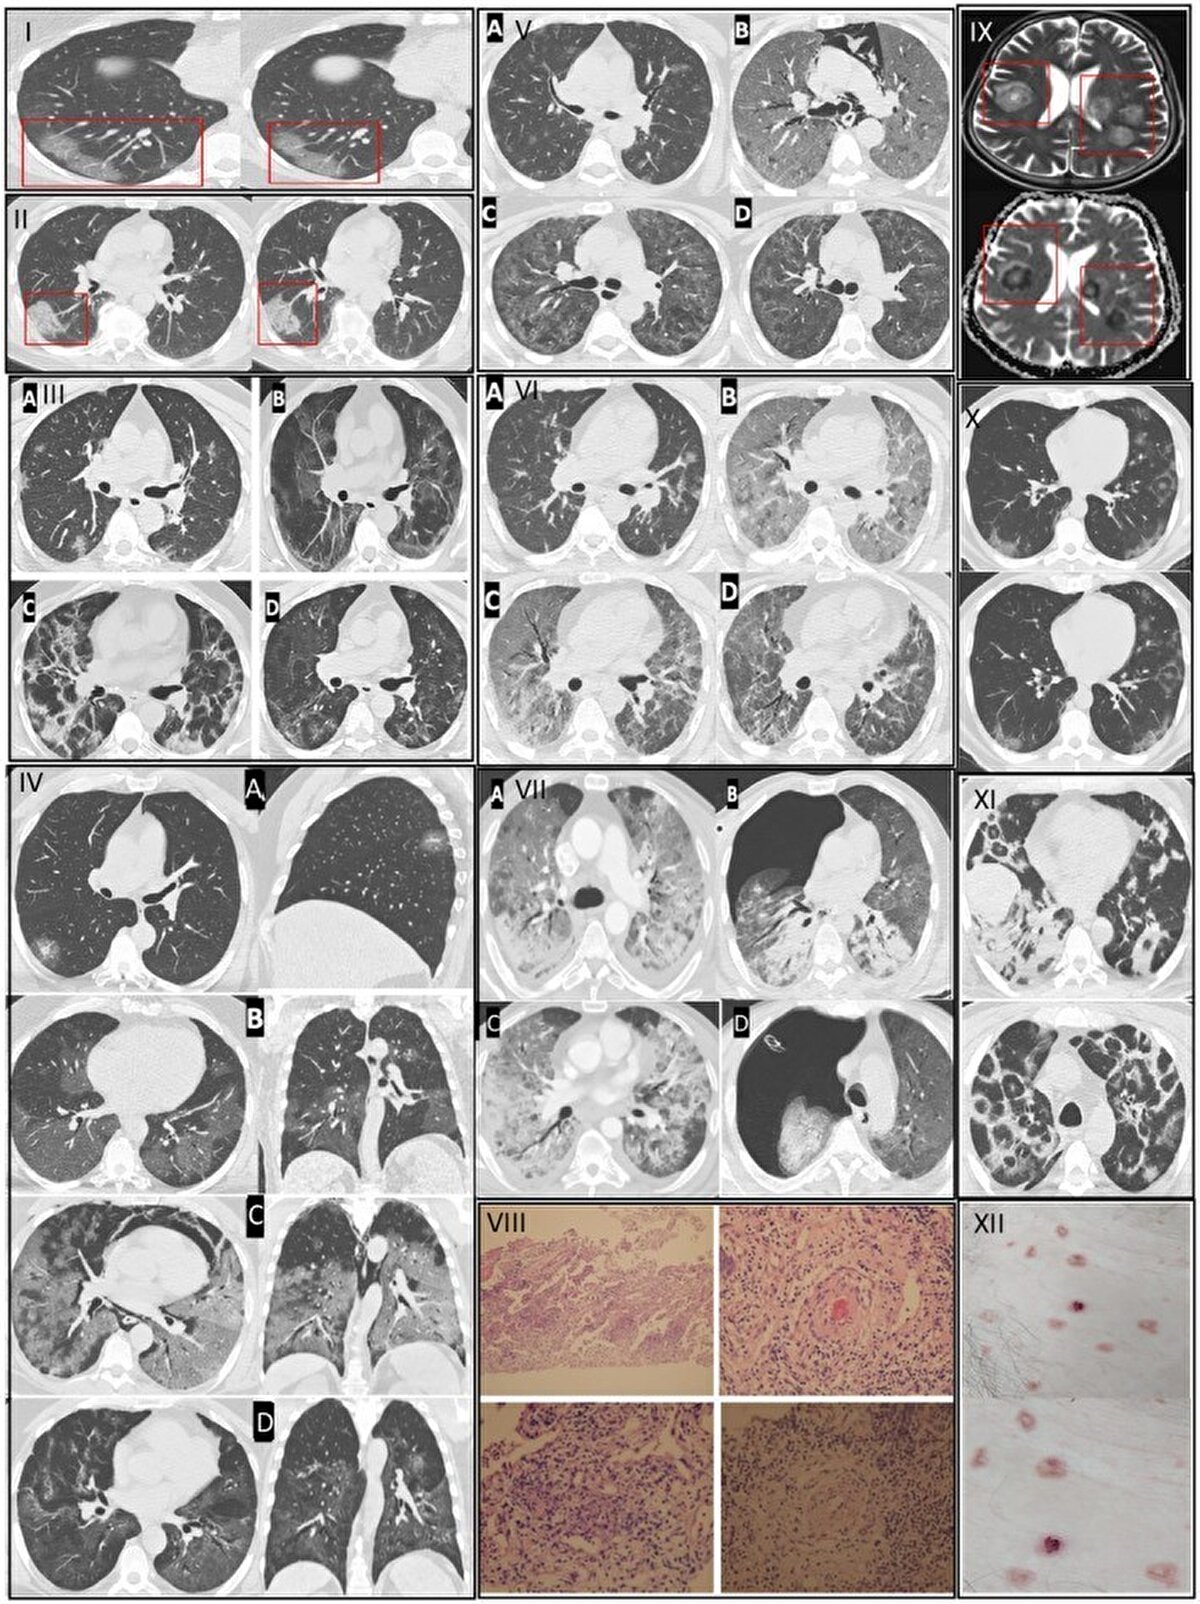

1-9

2-9

3-9

4-9

5-9

6-9